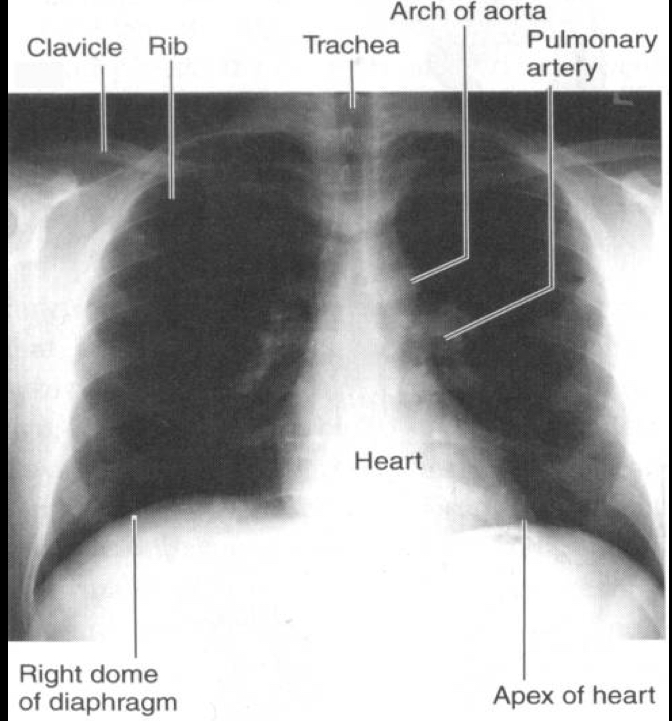

Oldest imaging techniques using an X-ray source and a film best for bones and picks up densities in tissues

Radiographs

term image